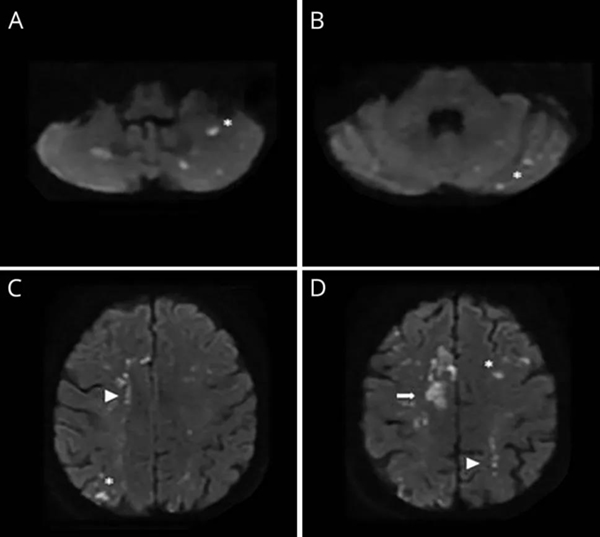

特鲁索综合征的典型影像学

多发性、双侧性、播散性的、前后循环均累及的DWI高信号病变,这个特征性的影像学表现称为“三流域征(Three Territory Sign)”。

三流域梗死的鉴别诊断

对于卒中发病时已经明确有肿瘤病史的患者,结合其影像学特征、血液高凝状态,做出特鲁索综合征的诊断相对容易。

但对于没有发现肿瘤的患者,表现为典型的三流域梗死,除了要认真筛查肿瘤外,还要注意鉴别其他可能的病因,文献中有报道系统性红斑狼疮、抗心磷脂抗体综合征、类风湿性关节炎等疾病,均可导致类似于散在点状梗死病灶的“三流域征”,临床工作中需要认真仔细地鉴别诊断。

特鲁索综合征相关的卒中患者影像学有一定特征性,常表现为“三流域梗死“,因此,在影像表现为三流域梗死的不明原因卒中患者中进行肿瘤筛查是必要的。